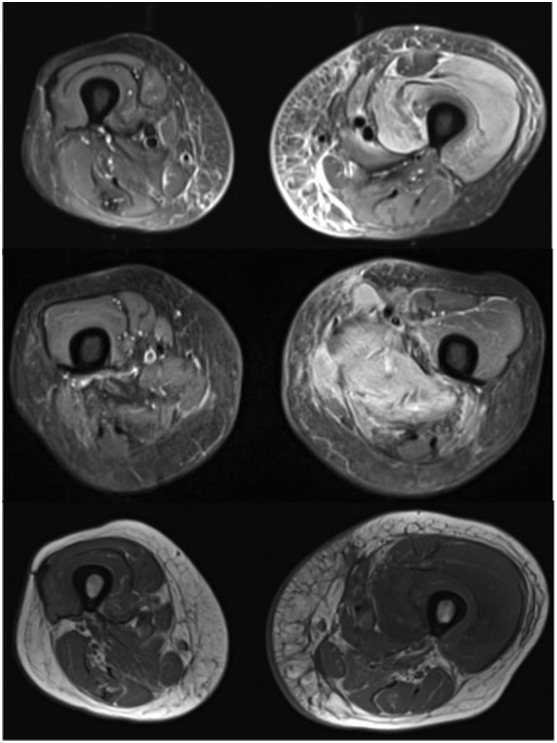

Her diabetes was poorly controlled on insulin, with her most recent HBA1c being 84 mmol/mol (21-42 mmol/mol). She had a normal White cell count with CRP of 159.1 mg/L (<5 mg/L) and CK 426 IU/L (<150 IU/L). A Doppler scan was negative for DVT and MRI (Figures 1 & 2) showed left thigh muscle oedema and necrosis affecting the anterior compartment. A possibility of pyomyonecrosis was suggested. To rule out the same, an ultrasound guided biopsy was performed. The aspirate revealed no growth from microbiology and histology revealed fiber atrophy, very few macrophages in the perimyosial connective tissue, and more importantly, thickened and hyalinised walls of small endomyosial and perimyosial capillaries with evidence of necrotic fibers. These findings are highly suggestive of necrotizing myopathy. With pipestem capillaries and minimal cellular infiltration, the possibility of an infective aetiology was ruled out.

Figure 1 T1 and T2 weighted cross sectional MRI of the both thigh showing increased signal intensity, skin and muscle edema affecting the anterior compartment of the left thigh.